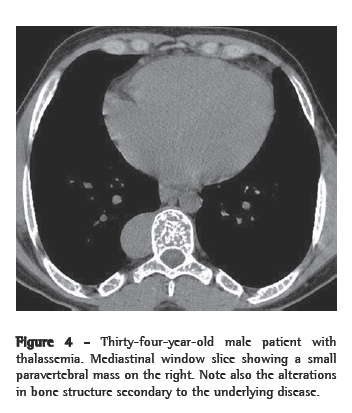

As associated findings, two patients presented calcifications in the spleen (Figure 4). Both of them had sickle cell anemia. Two of the six patients had undergone splenectomy, and two presented normal spleen imaging findings. Bone alterations related to the underlying disease were identified in three patients.

On CT scans, masses with dense soft parts, usually homogeneous, with characteristics similar to those described using conventional radiology,(1,2,5,6) and which might or might not be highlighted after administration of contrast material,(4,10) can be seen. This imaging method is important for analyzing the internal structure of the lesions, especially of those that are rich in fat,(5) in order to identify other paracostal masses, and for detecting bone alterations associated with certain hematologic diseases, such as thalassemia and sickle cell anemia.(6) In cases related to thalassemia, sickle cell anemia, or myeloid metaplasia, there can be widening of the medullary cavities of the ribs.(5) All of those aspects were identified in our cases. It is of note that two patients presented calcifications in the spleen, resulting from multiple infarcts, with autosplenectomy. Both of those patients had sickle cell anemia. This finding can also facilitate the differential diagnosis.